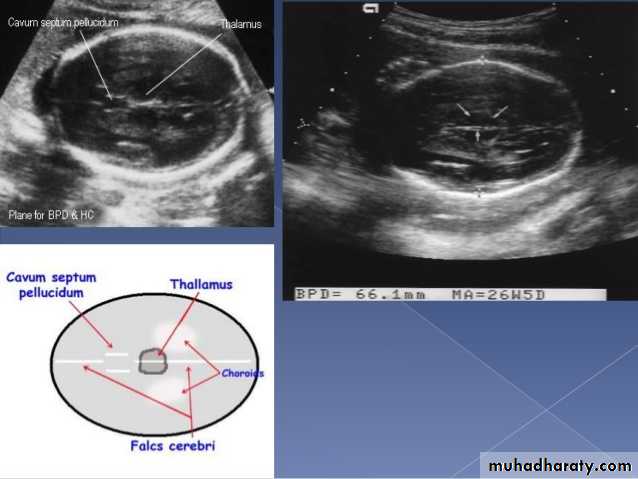

Mosul Medical College /radiology department2016BPD together with head circumference (HC), abdominal circumference (AC), and femur length (FL) are computed to produce an estimate of fetal weight. In the second trimester this may be extrapolated to an estimate of gestational age and an estimated due date (EDD) .

The BPD should be measured on an axial plane that traverses the thalami, and cavum septum pellucidum. The transducer must be perpendicular to the central axis of the head, and thus the hemispheres and calvaria should appear symmetric.